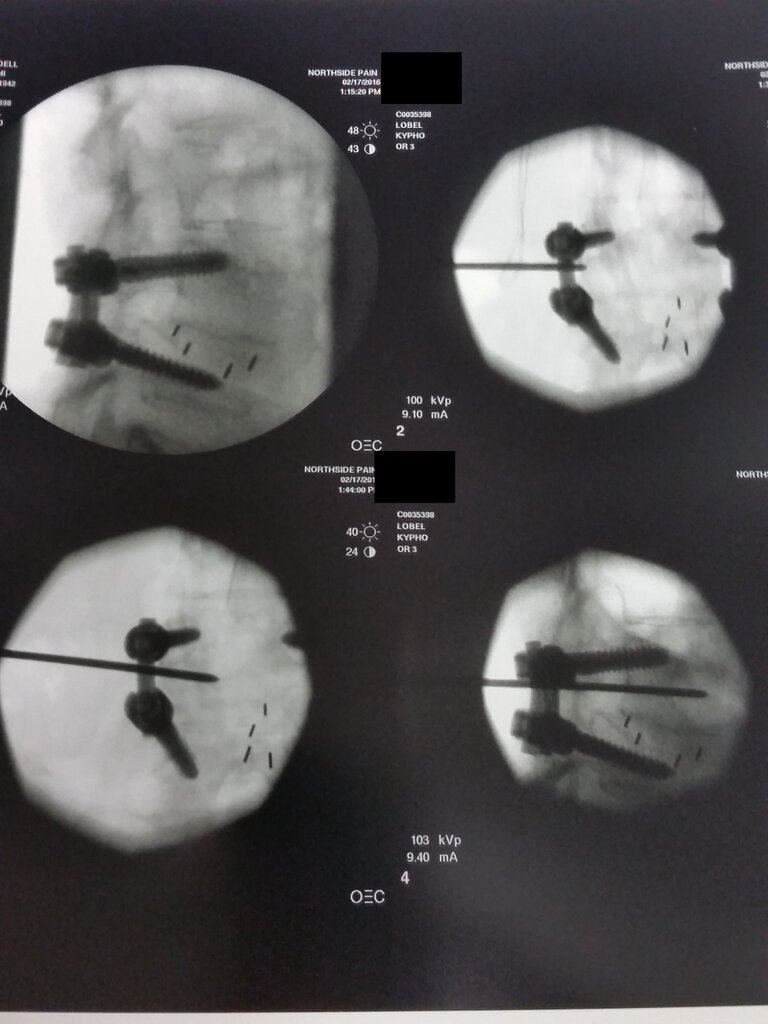

83 y/o F with new L5 compression fracture from 2 months back (30% superior endplate compression) with fracture lines that extend into the bilateral pedicles, L>R.

I want to fix this thing, but she also has history of L4-S1 posterior fusion with bone graft (fusion done in 1975) going right over the pedicle shadow. Hard to make out any definable anatomy needed on left, but I do see my landmarks on right.

Terrible job reducing the anterolisthesis, Steve! You need to go back to surgery school.

Steve you’re a total badass. And whoever did that fusion sucks! Seriously the screws are shooting up out of the superior end plate and there’s really no restoration of sagittal balance